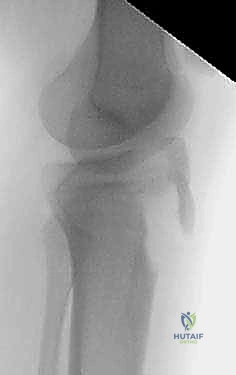

2. التصوير بالأشعة السينية (X-Rays)

هو الخطوة التشخيصية الأساسية. يتم أخذ صور من زوايا متعددة (أمامية خلفية AP، وجانبية Lateral). الصورة الجانبية هي الأكثر أهمية لأنها تظهر بوضوح مدى انفصال (انزياح) حدبة الظنبوب عن مكانها الطبيعي، وتظهر أيضاً ارتفاع الرضفة (Patella Alta).